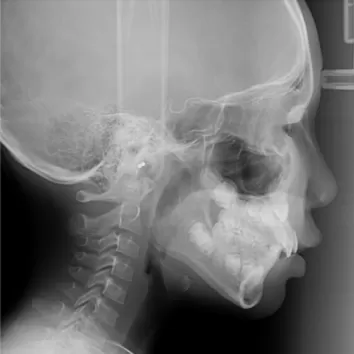

Rayons X avant le traitement

[Radiographie panoramique/Céphalogramme latéral]